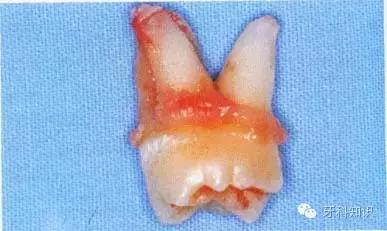

4.断根拔除出:首先要了解每个牙的牙根数目和分布情况。拔除断根时应根据不同情况采取不同方法。如断根边缘露于牙槽骨之间,将牙根挺出。断根位于牙槽窝内或部位很深者,则用骨凿凿除一部分根周骨壁,形成缝隙,然后插入根挺或根尖挺,将断根挺出(图5-12)多根牙折断牙根尚聚在一起者,可用骨凿将联结处劈,分成几个单根,然后分别取出(图5-13、5-14),上述方法仍难拔出的断根,可切开并翻起颊侧粘骨膜瓣,凿除部分颊侧骨质,暴露牙根,然后取出断根,缝合粘骨膜瓣及牙龈。

图5-12 断根拔除法示意图